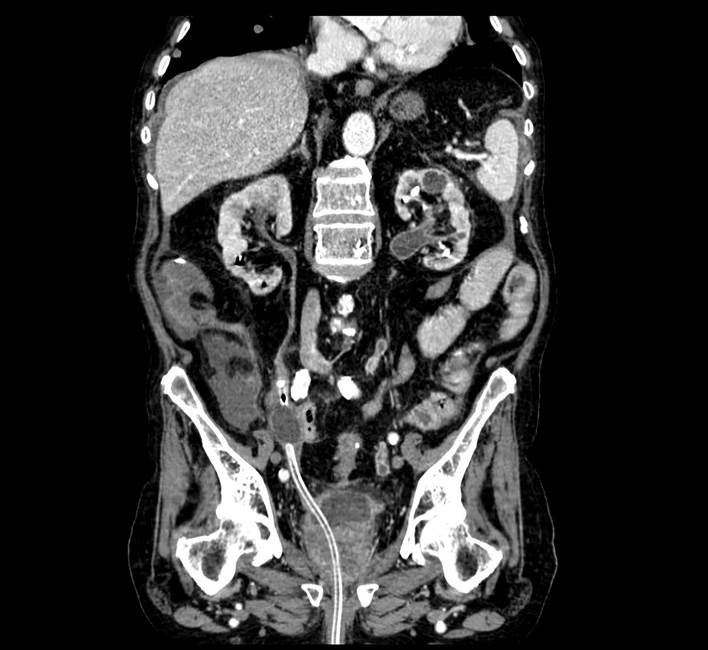

An 85-year-old patient had a past medical history of high blood pressure and chronic obstructive pulmonary disease, as well as long-term indwelling urethral catheters due to urinary retention and voiding dysfunction, most likely secondary to myasthenia gravis. The patient was admitted to our emergency department because of abdominal pain in the hypogastrium, dysuria, and the diagnosis of septic shock from extended-spectrum beta-lactamase-producing Escherichia coli after Foley catheter replacement. The patient had poor progression, presenting with persistent pain, despite analgesic treatment, and oligoanuria. Urgent ultrasound identified the absence of the Foley catheter balloon in the bladder. Abdominal-pelvic computed tomography (CT) revealed a Foley catheter at the right ureter (Images 1 and 2). The bladder catheter was replaced without incident. Patient progression was good, after antibiotic treatment, with no incidents resulting from later indwelling Foley catheter replacements.

A 75-year-old patient had a past medical history of high blood pressure, atrial fibrillation, mitral insufficiency, chronic obstructive pulmonary disease, and T1GII urothelial bladder carcinoma and was admitted to our department due to hematuria and anemia. Transurethral resection of the bladder (TURB) was performed and bilateral ureteral reflux and bilateral hydroureteronephrosis were diagnosed. The patient presented with persistent hematuria and abdominal pain in the postoperative period. Abdominal and pelvic CT identified a Foley catheter at the right ureter (Images 3 and 4). It was removed and replaced with no incidences and the patient’s postoperative progression was good.

Ultrasound imaging of the bladder can be performed as a first method to confirm the location of the catheter and its balloon, but the technique of choice is CT to evaluate possible complications and the need for subsequent intervention.8 Ultrasound was not conclusive in our patients and CT was essential for making the diagnosis.